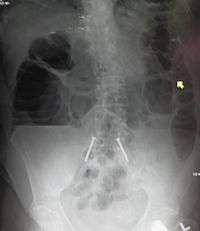

The main diagnostic tools are blood tests, X-rays of the abdomen, CT scanning, and/or ultrasound. If a mass is identified, biopsy may determine the nature of the mass.

Radiological signs of bowel obstruction include bowel distension and the presence of multiple (more than six) gas-fluid levels on supine and erect abdominal radiographs.

Contrast enema or small bowel series or CT scan can be used to define the level of obstruction, whether the obstruction is partial or complete, and to help define the cause of the obstruction.

Some causes of bowel obstruction may resolve spontaneously;[12] many require operative treatment.[13] In adults, frequently the surgical intervention and the treatment of the causative lesion are required. In malignant large bowel obstruction, endoscopically placed self-expanding metal stents may be used to temporarily relieve the obstruction as a bridge to surgery,[14] or as palliation.[15] Diagnosis of the type of bowel obstruction is normally conducted through initial plain radiograph of the abdomen, luminal contrast studies, computed tomography scan, or ultrasonography prior to determining the best type of treatment.[16]